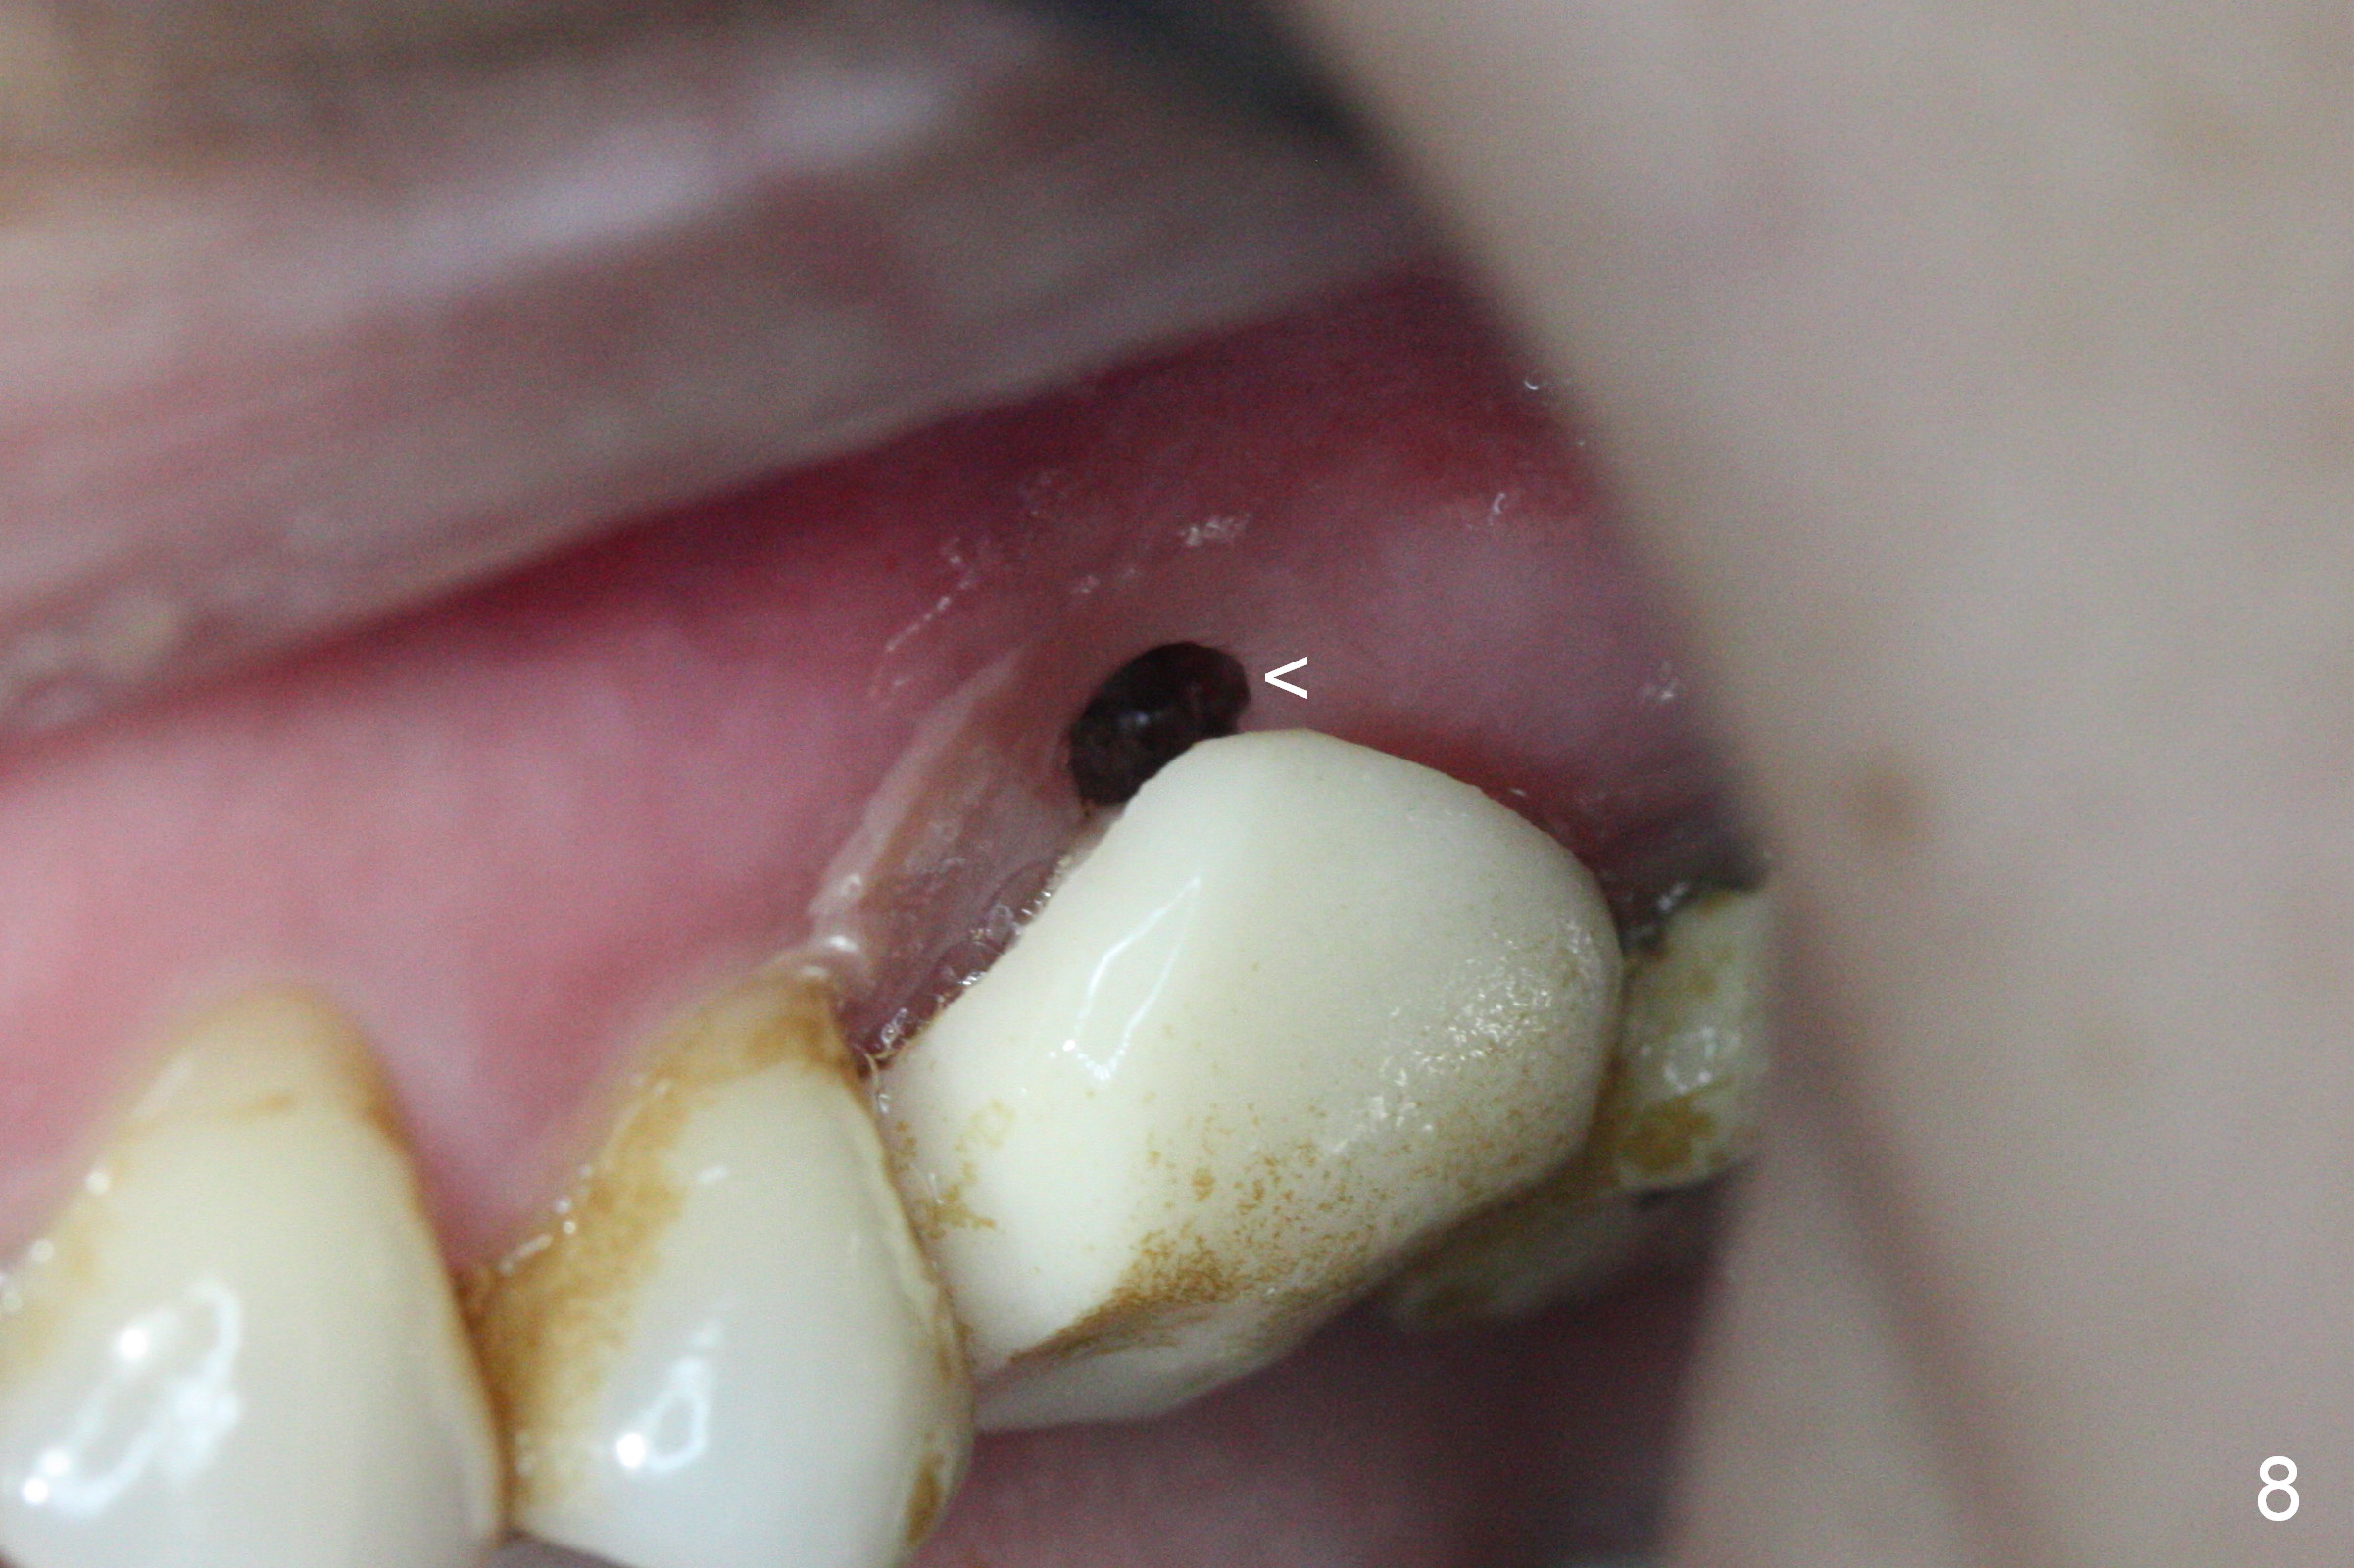

There is abundant subgingival calculus on the surfaces of the extracted tooth at #14 (Fig.1: P: palatal; MB: mesiobuccal), corresponding to the large empty socket (Fig.2 without septal bone, the buccal plate being low). Osteotomy is established palatally with Magic Expander (ME) 3.0 mm for ~ 3 mm deep (Fig.3,4) with minimal stability so that it moves during X-ray taking (Fig.4). Since the bone is dense, Magic drill 4.3 mm is used after application of ME 3.8 and 4.3 mm to complete sinus lift (Fig.5 (panoramic X-ray)). A 5x11 mm implant is placed with ~ 30 Ncm, followed by insertion of 6.5x4(3) mm Hexa abutment, bone graft and collagen membrane (Fig.6). The latter is kept in placed with an immediate provisional with clearance from the opposing dentition (Fig.7 *). Between the 1st and 3rd weeks postop, the buccal gingiva recedes with loss of bone graft (Fig.8 <) and implant thread exposure (Fig.9 * (A: abutment)). After inducing hemorrhage, allograft is placed (Fig.10 >), followed by collagen dressing (Fig.11 >). The wound closes by adding new acrylic (Fig.12 *). Thirteen days later, food is trapped in the buccal gap (Fig.13 ^). It appears that the provisional does not help wound healing. The provisional and abutment are removed; incorporating bone graft (Fig.14 *) and the implant are exposed. After placing collagen plug against the bone graft and implant, the wound is closed by periodontal dressing.